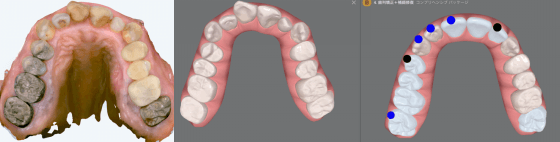

当院では、体の歪みを調べ、その方にとって無理のない安定した顎位を見つけ出し、その位置で噛み合わせを構築することを重要視した矯正治療を行っています。